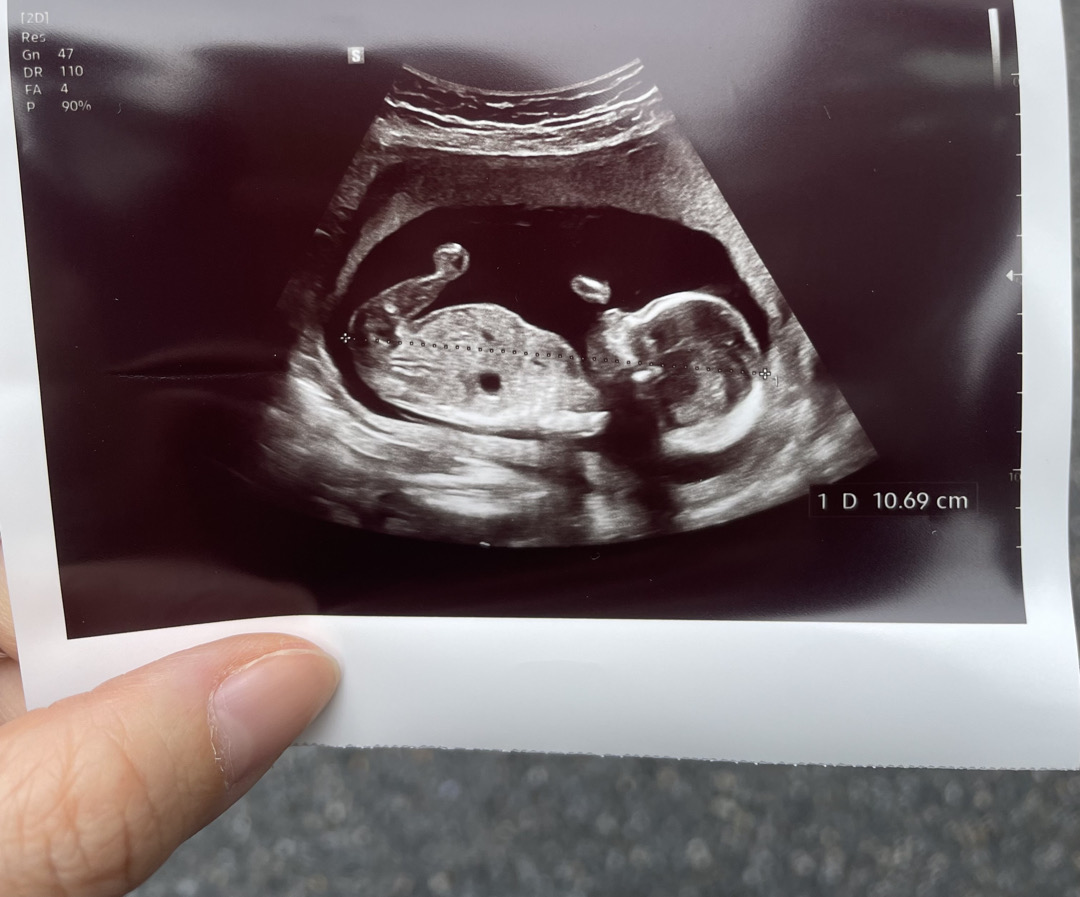

몸에 까만 동그란부분은 어디일까용?-?

오늘 오랜만에 병원다녀왔어요 ㅎㅅㅎ 16주진입이네요:) 참 시간이 안가요ㅎㅎ 심박수 체크할때 심장은 저 까만 동그란부분보다 윗부분이었어서 심장은 아니더라구요!! 어느 장기일까요…?? 궁금해요..💗

의사쌤이 매번 저 검정 동그라미는 위라고 얘기해주셧어요 !

저 위치면 위장이 맞을것 같아요~ 초음파 보다보면 심장 반대편 살짝 아랫쪽 검은 동그라미가 위장이고 더 밑에 검은 동그라미 하나 더 있는게 방광이라고 설명해주셨어요~

앗 저두 병원다녀왔는데! 교수님이 말씀하길 검은색으로 보이는거는 애기가 양수를 먹어서 위가 검은색으로 보이는거라구 했어요~ 제 초음파랑 비슷해서 아마도 위가 아닐까싶어요!

저도 16주차에 병원 다녀왔는데 저렇게 장기가 보였어요~ 아기 실루엣이 넘 귀엽네요 의사선생님이 장기 설명해 주셨었는데, 아마 위 아니면 간 같아요! 크기가 커서 위 같기도 한데... 의학적 지식이 없는 제 단순 추측이에요ㅎㅎ